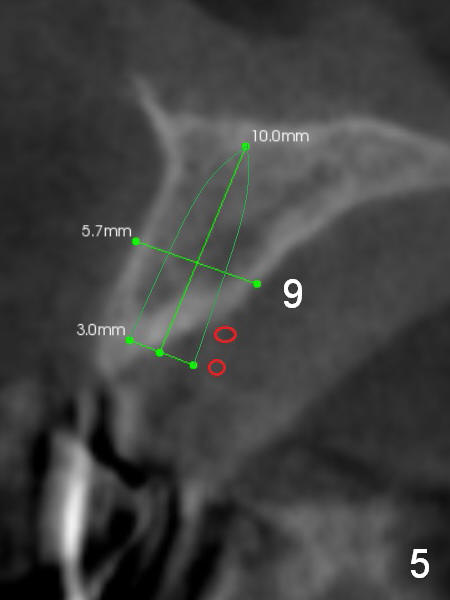

A 69-year-old man would consider implant option for his upper front teeth (Fig.1: #5-9) if there is no separate bone graft procedure. He does not want implants for his lower left molars (#18,19), since he has had a partial denture. In fact the bone at #5-9 is so thin that 2-3 mm 1-piece implants can be placed at #5,7 and 9 (Fig.2-5 (CT coronal sections (B: buccal)) for a 5-unit bridge (Fig.1). To support and increase the longevity of the latter, implants at #18,19 are mandatory (Fig.6,7).

Wheel saws will be used to split the ridge before drilling at #7 (Fig.4). Surgical bur is to be used for ridge reduction prior to osteotomy at #19 (Fig.6), while at #18, osteotomy depth will be 10 mm for 8 mm implant (Fig.7).